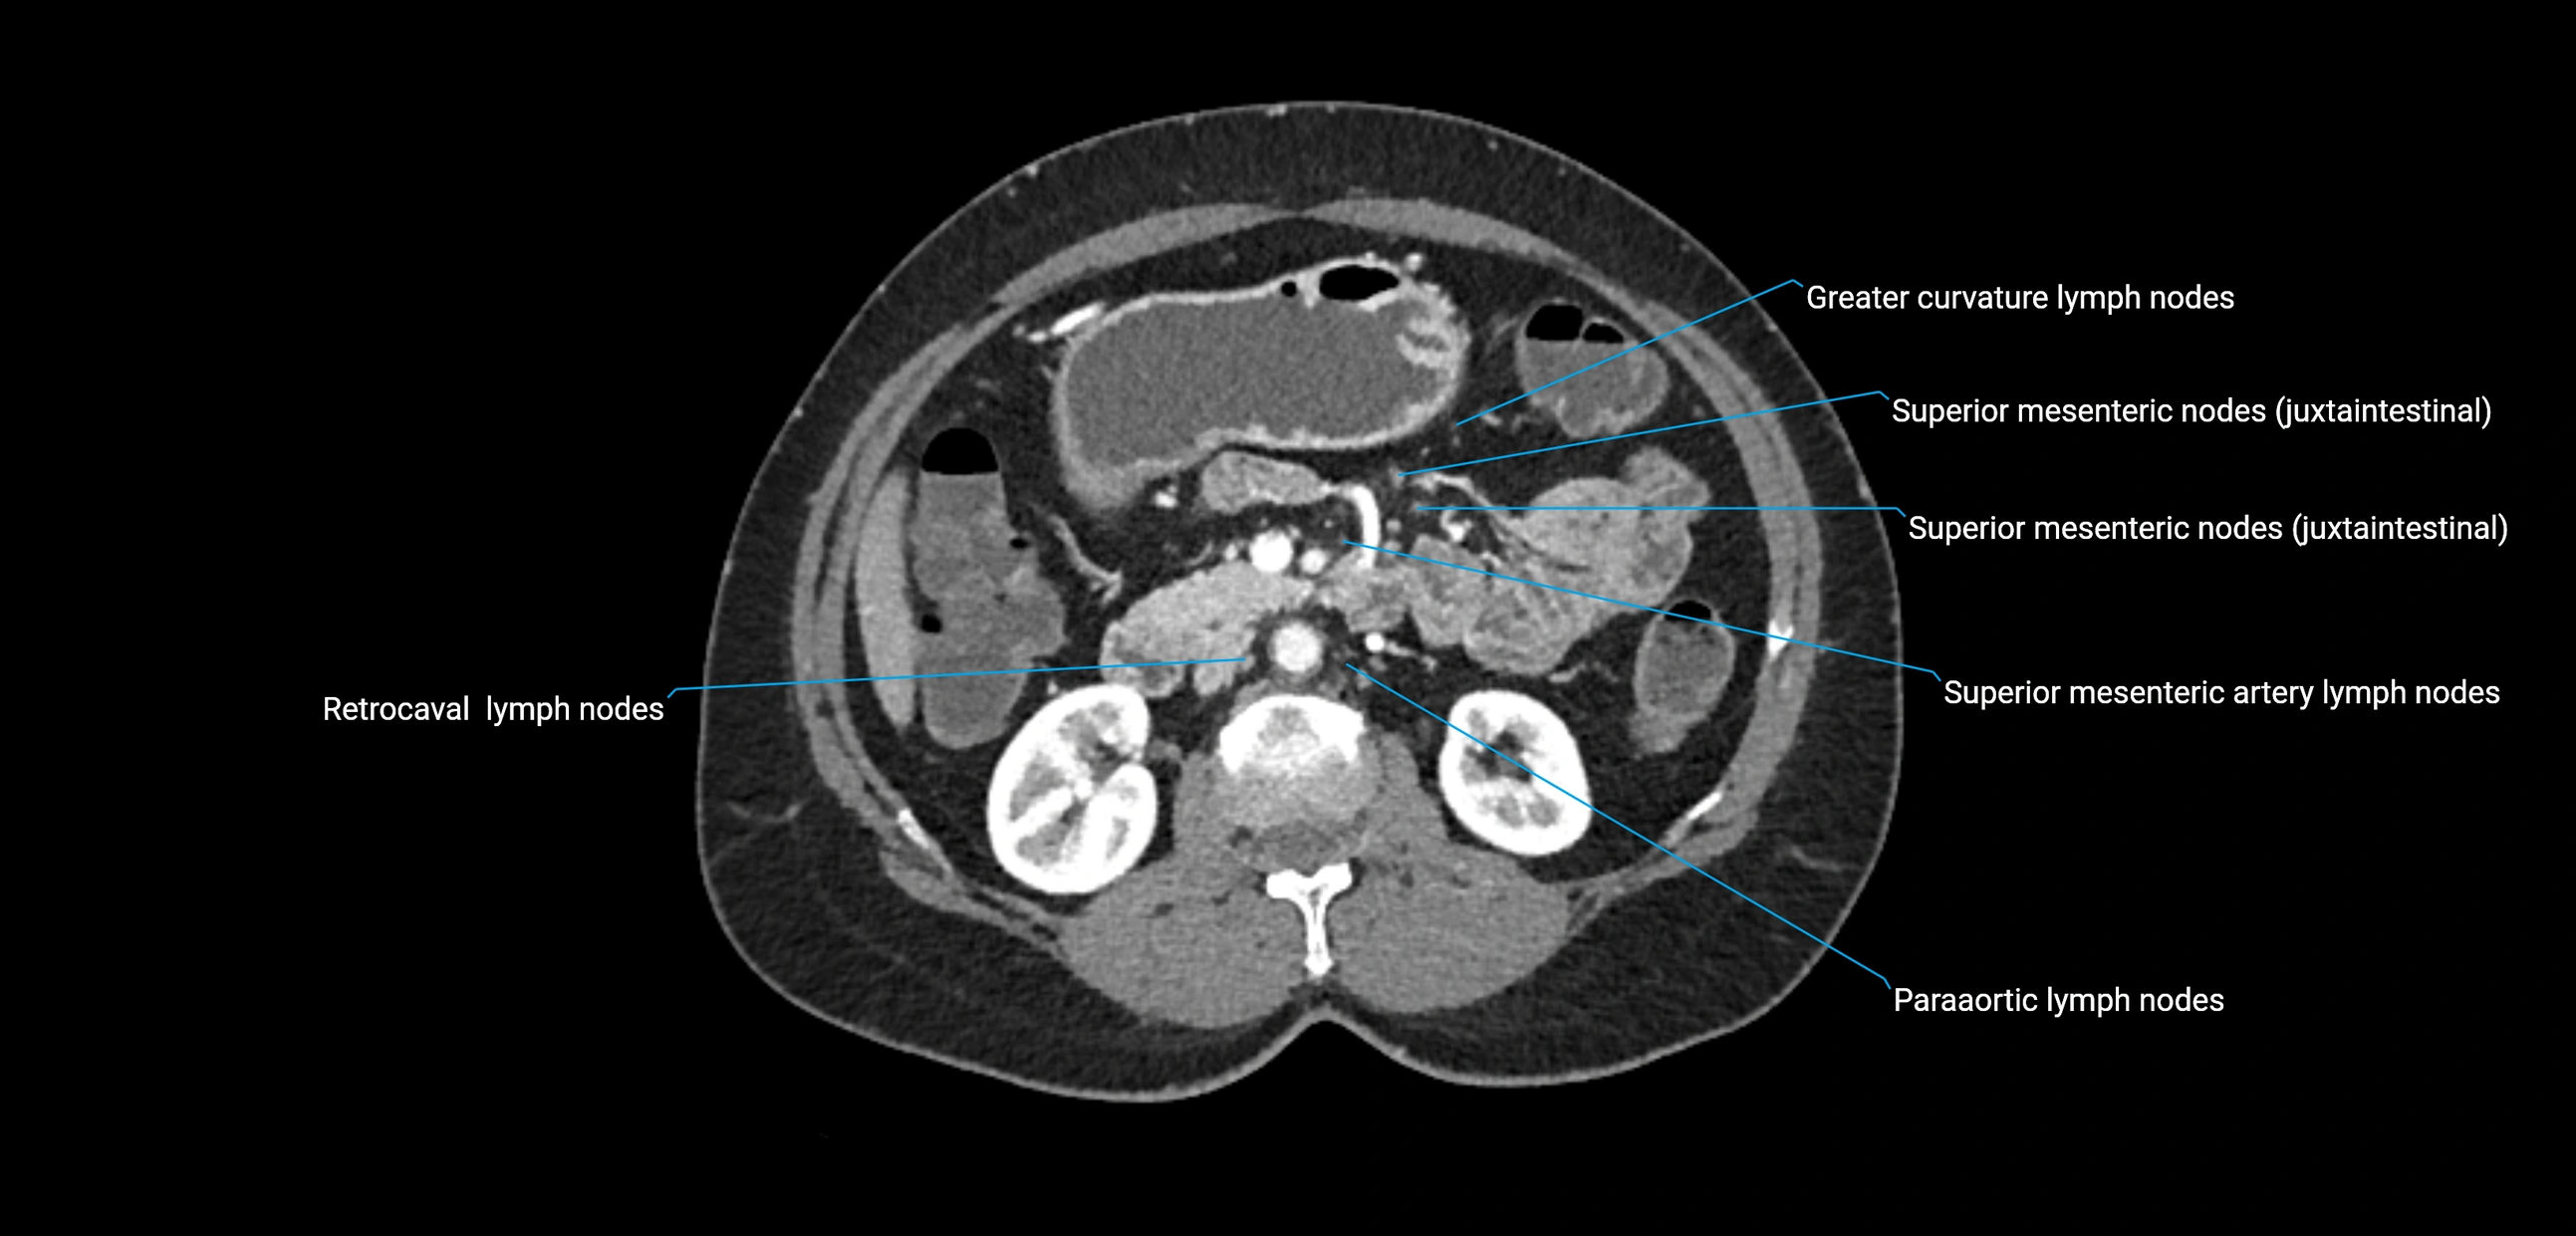

CT Appearance

CT Pre-Contrast:

• Nodes appear as soft-tissue density nodules adjacent to the aorta and IVC

CT Post-Contrast:

• Normal nodes enhance homogeneously

• Malignant nodes may show heterogeneous enhancement, central necrosis, or conglomerate formation

• Size >1 cm short axis is suspicious, though morphology and distribution are equally important

CT image

image